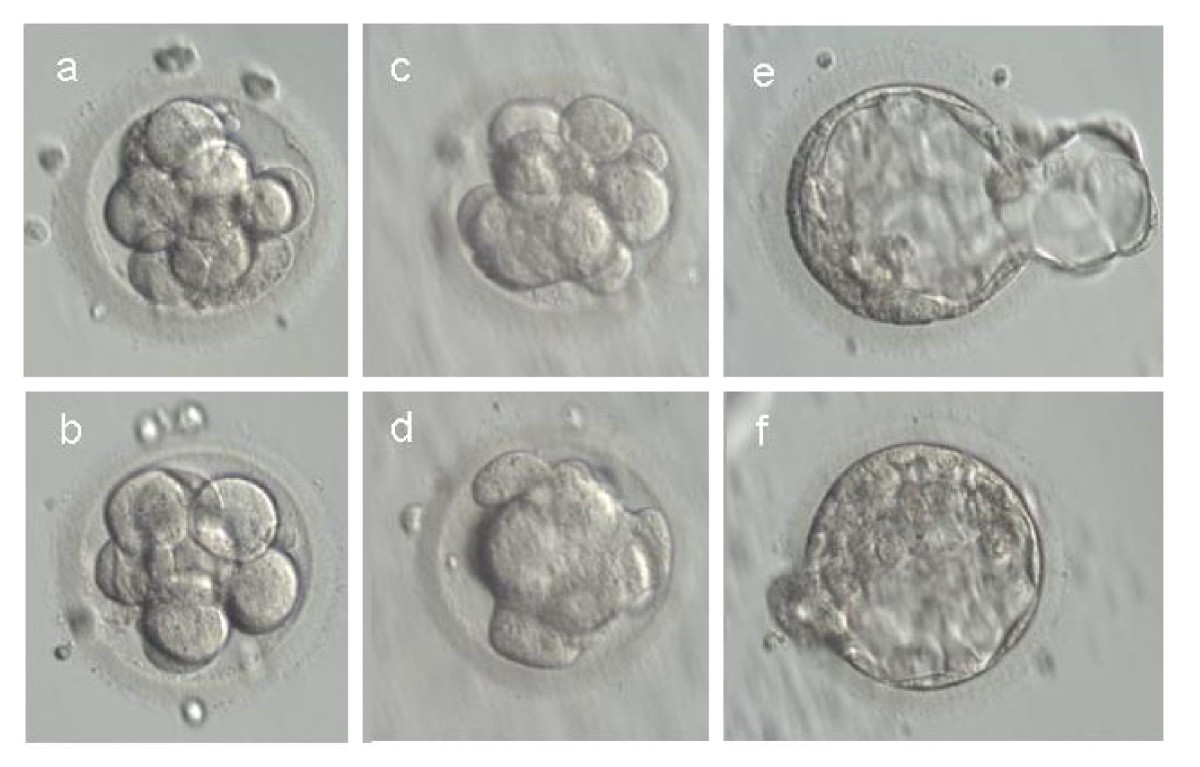

На 5 день эмбрион уже активно делится на клетки, формируя структуру, известную как бластоциста. Это важный этап для успешной имплантации в матку.

Визуально бластоциста на 5 день под микроскопом выглядит как пузырёк с жидкостью и группой клеток, которые постепенно организуются в будущие ткани.

Фотографии бластоцисты на 5 день помогают врачам и исследователям оценить качество эмбриона перед его возможной имплантацией.

Развитие эмбрионов в режиме реального времени

Микроскопические изображения бластоцисты помогают медицинским специалистам исключить возможные аномалии и выбрать самые здоровые эмбрионы для трансплантации.

Для точной диагностики и планирования дальнейших шагов в процессе ЭКО врачи внимательно анализируют бластоцисту, обращая внимание на её форму и состав клеток.